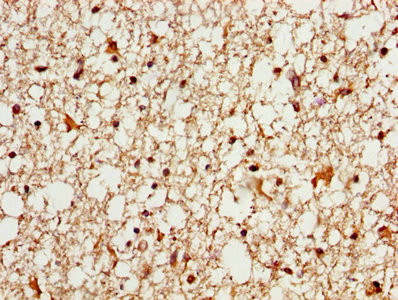

IHC image of CSB-PA013322LA01HU diluted at 1:600 and staining in paraffin-embedded human brain tissue performed on a Leica BondTM system. After dewaxing and hydration, antigen retrieval was mediated by high pressure in a citrate buffer (pH 6.0). Section was blocked with 10% normal goat serum 30min at RT. Then primary antibody (1% BSA) was incubated at 4°C overnight. The primary is detected by a biotinylated secondary antibody and visualized using an HRP conjugated SP system.